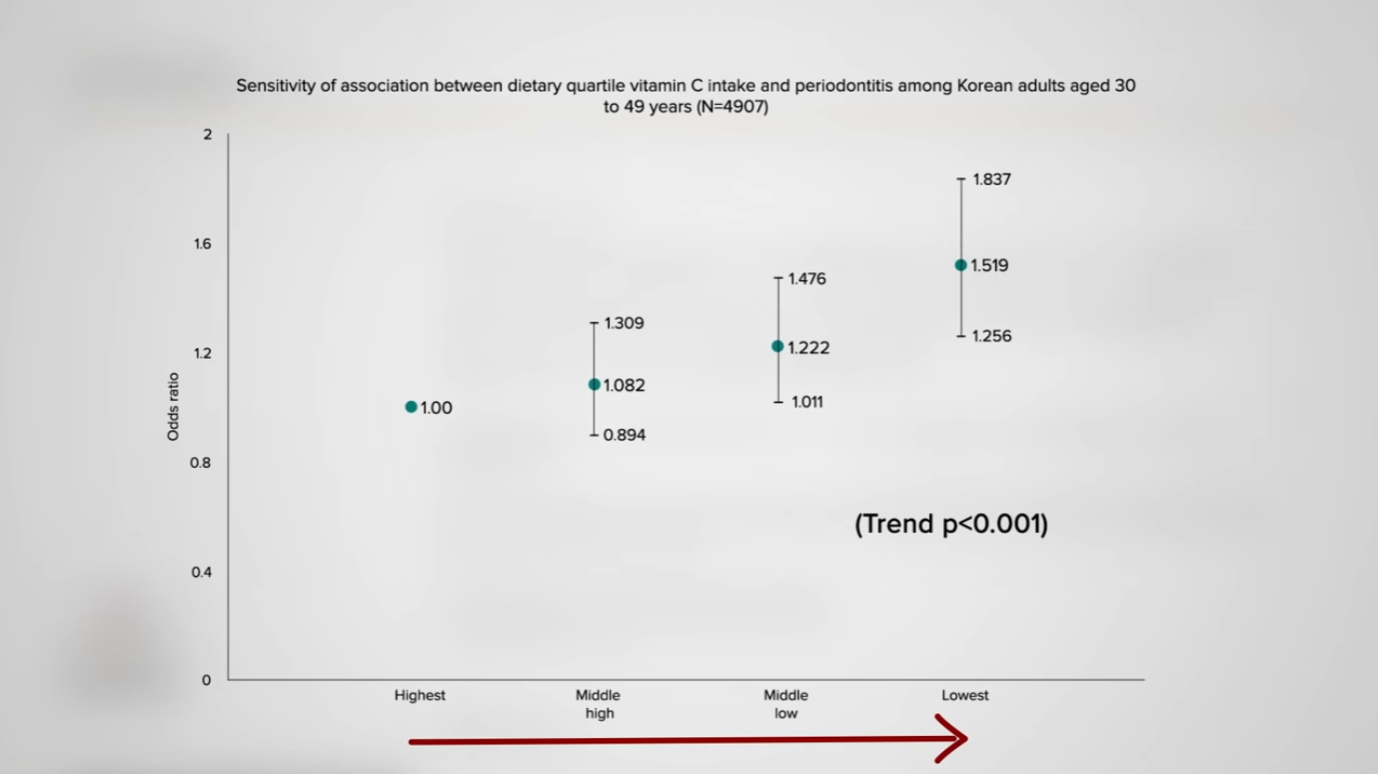

Is there an association between periodontitis and dietary vitamin C intake? Apparently so, as you can see in the graph below and at 3:34 in my video. Increased risk of periodontitis has been associated with lower levels of vitamin C intake. What effect might vitamin C depletion and supplementation have on periodontal health? Researchers provided controlled amounts of vitamin C to study participants for three months and found that measures of gum inflammation were directly related to the subjects’ vitamin C status. On about one orange’s worth of vitamin C a day, their gums improved; down around only 5 mg a day, though, their gums got worse. On ten oranges’ worth of vitamin C a day, they got better and then worse once again when the vitamin C level dropped down to five oranges’ worth, as you can see in the graph below and at 4:01 in my video. The study was pretty convincing, though 5 mg a day is down at scurvy level. We know our gums start bleeding and our teeth can fall out if we have scurvy, but that doesn’t mean taking extra vitamin C helps.